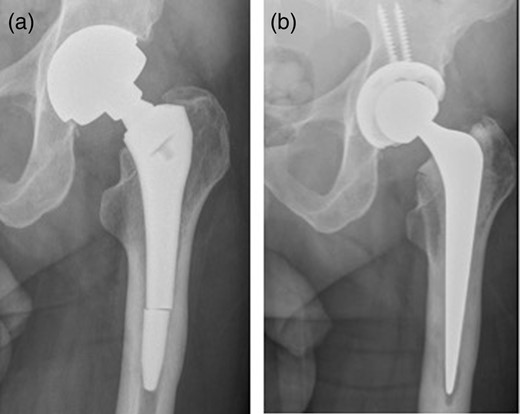

A 74-year-old man presented to our MoM surveillance clinic with sudden onset of severe left hip pain. Five years prior to presentation, he had undergone a left MoM THR with a Profemur stem and Procotyl cup (Wright Medical Ltd, UK). The patient also had undergone a right THR with a similar prosthesis 6 years prior to this presentation. One year prior to presentation, he was noticed to have raised metal ions (cobalt and chromium) and X-ray of his left hip showed radiolucent lines in Zones 1 and 7. While awaiting an MRI scan, he contacted our clinic complaining of sudden severe left hip pain without history of trauma. X-ray of his left hip showed a distal stem fracture (Fig. 1a). He was admitted from the clinic and his left hip was revised with ceramic on polyethylene bearing using Exeter stem and Trident cup (Stryker UK Limited; Fig. 1b).

(a) Distal stem fracture of left hip prosthesis. (b) Post-revision X-ray.